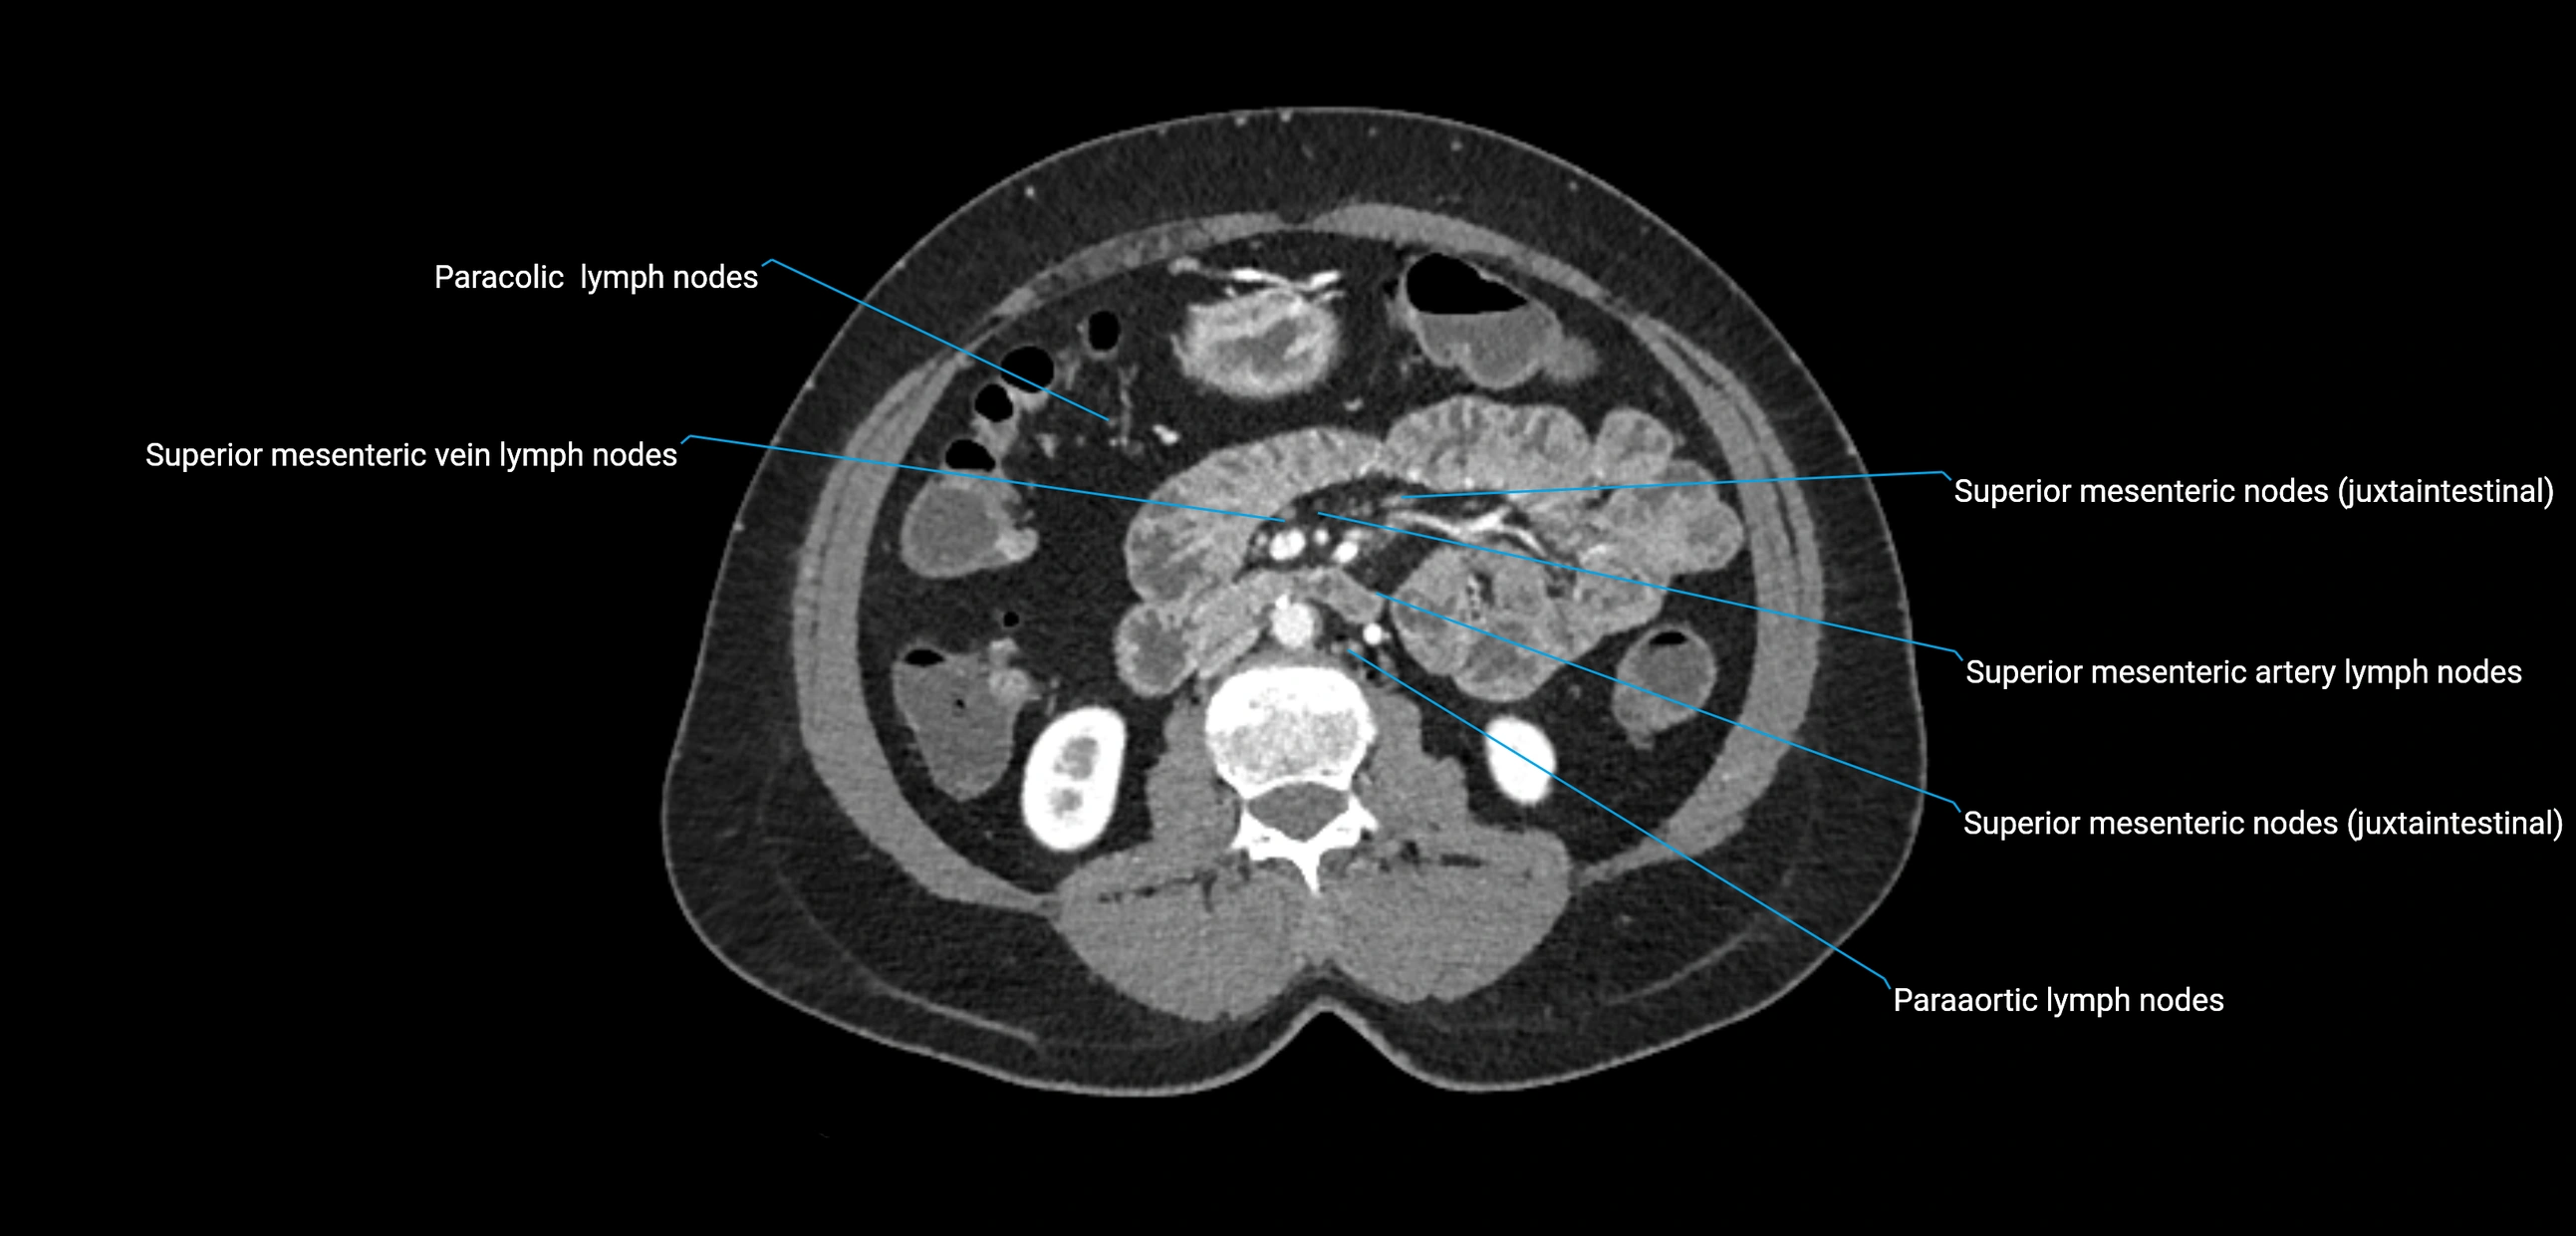

CT Appearance

CT Pre-Contrast:

• Nodes appear as soft-tissue density nodules adjacent to the aorta and IVC

• Calcification may be seen in chronic infections (e.g., tuberculosis)

CT Post-Contrast:

• Normal nodes enhance homogeneously

• Malignant nodes may show heterogeneous enhancement, central necrosis, or conglomerate formation

• Size >1 cm short axis is suspicious, though morphology and distribution are equally important